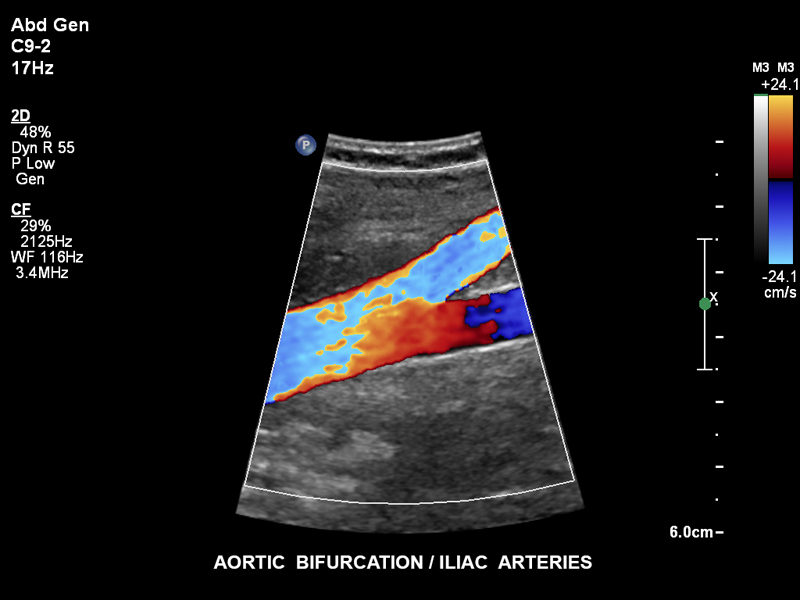

Бифуркации аорты, С9-2